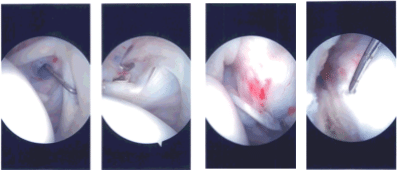

Intraoperative Arthroscopy Images

The arthroscope was removed and re-inserted into the subacromial space. A shaver was introduced from the anterosuperior portal. A Bursectomy was performed. Examination of the rotator cuff showed a partial rotator cuff tear on the bursal side. There was no fraying of the acromion.

The AC joint did not show any arthritis. Decision was taken not to do distal clavicle excision. The plane of the rotator cuff tear was implanted. Lateral entry anterior portal was made. We completed the bursectomy.

The implant was introduced from the lateral portal and seemed to cover the rotator cuff tear. A separate portal was made to pass the tracks. A sleeve was inserted followed by multiple tacks to hold the implant in place.

The handle was removed. The lateral part of the implant was fixed to the bone with the use of bone anchors x2. Final pictures were taken and saved.